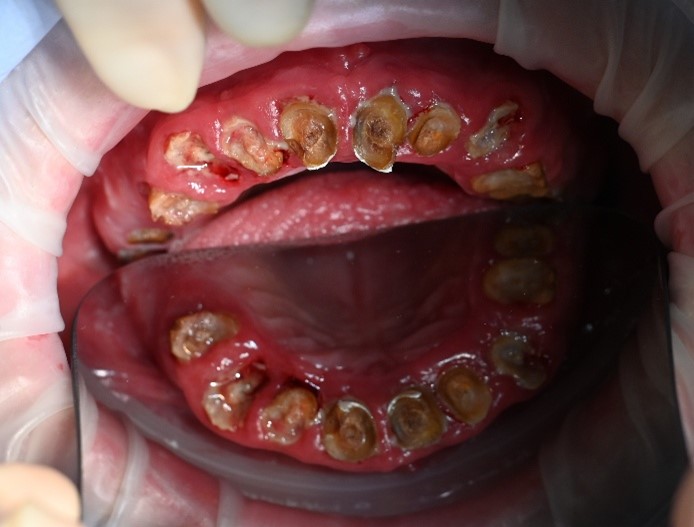

We carried out a comprehensive clinical assessment and gathered detailed diagnostic records, including:

• clinical photographs

• intraoral scans and photos

• OPG x-ray

• CBCT scan

• digital implant planning records

These records allowed us to carefully evaluate bone levels, gum health, and ideal implant positioning.

Although the patient showed moderate bone loss in certain areas and signs of previous chronic infections, his overall bone quality remained suitable for implant treatment. Importantly, there was no active infection at the time of surgery.